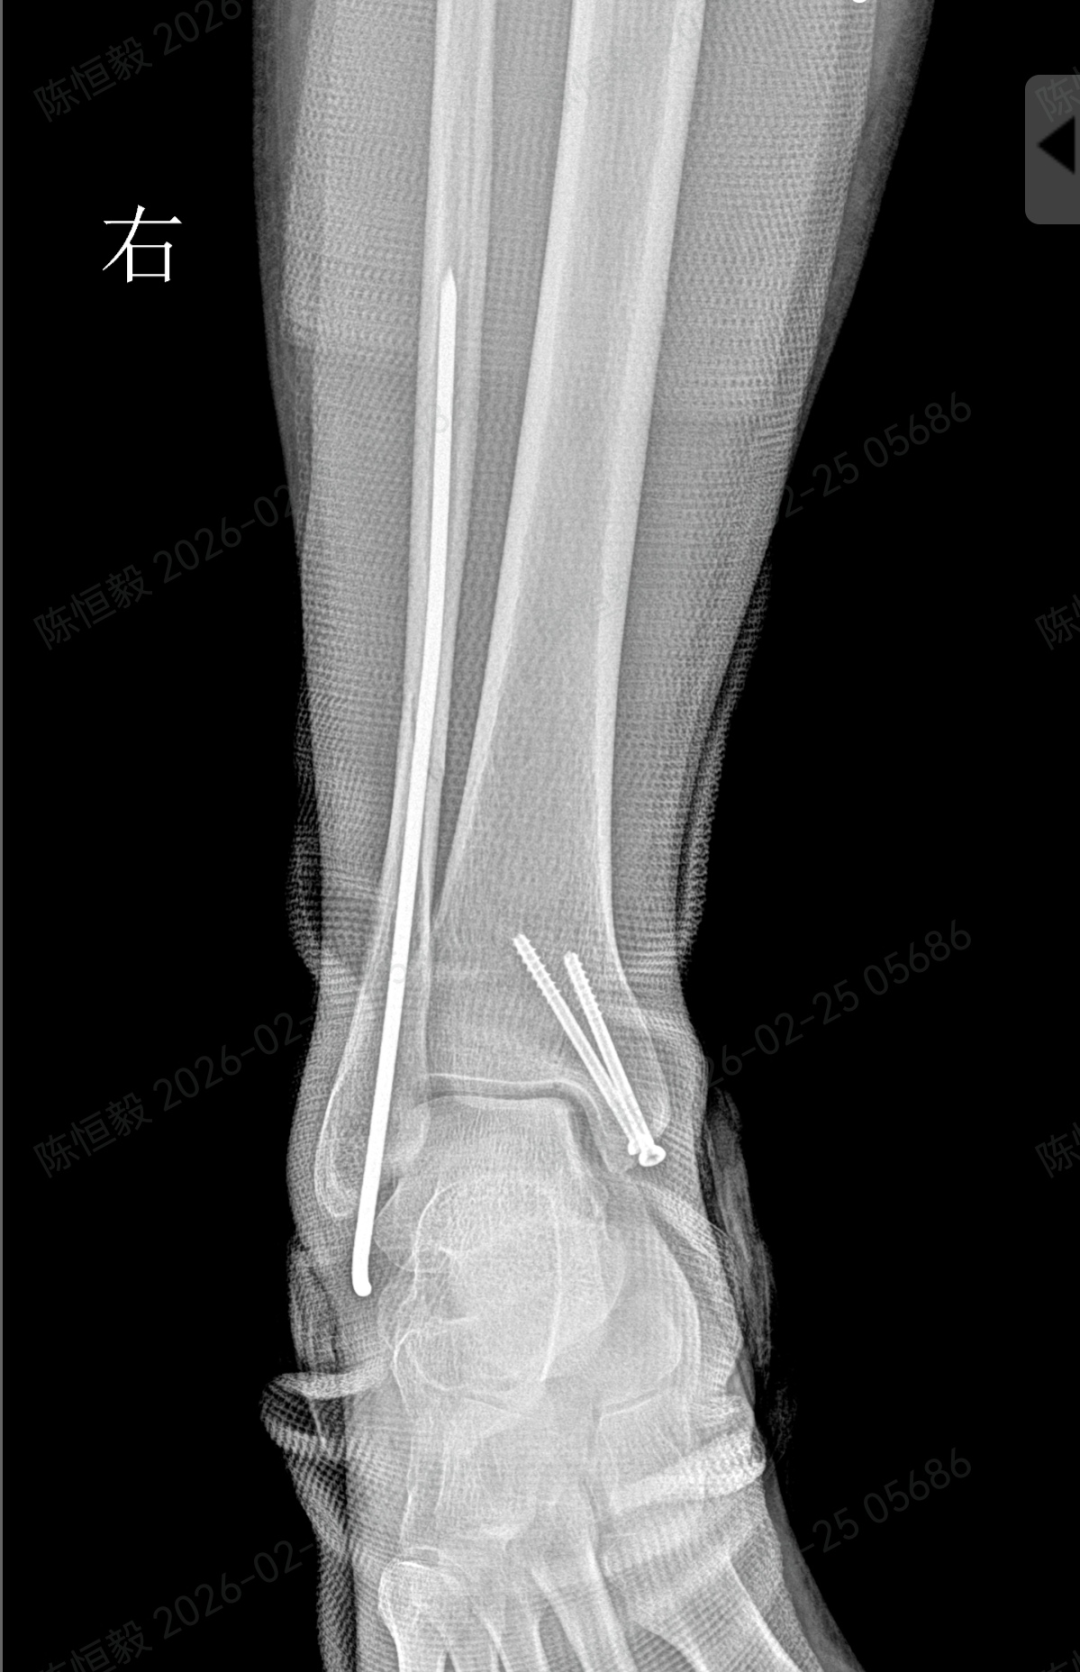

针对王女士的踝关节骨折情况,由副主任医师陈涛主刀,足踝外科团队为其实施了关节镜辅助下机器人导航微创闭合复位内固定术。

依托机器人导航系统,规划螺钉置入通道,避开关节面与重要组织;

最后通过另外两个 5 毫米的小孔置入空心螺钉,完成骨折端的稳定固定。

整个手术仅通过三个 5 毫米的小切口完成,最大程度降低了手术创伤。